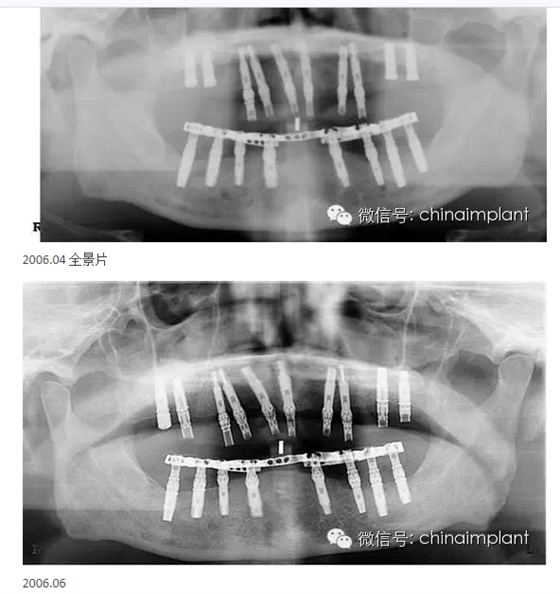

此案例為術(shù)后兩周戴臨時(shí)牙。過去因?yàn)閾?dān)心感染的問題,一個(gè)月以內(nèi)帶臨時(shí)牙也叫做即刻負(fù)重或者早期負(fù)重。(現(xiàn)在當(dāng)天戴臨時(shí)牙(即刻復(fù)重)的情況也非常常見).

本案例已經(jīng)將近10年了(2005年12月),但是修復(fù)效果個(gè)人認(rèn)為很不錯(cuò),所以拿出來和大家分享。

從修復(fù)全景片上看到牙齒排列非常好